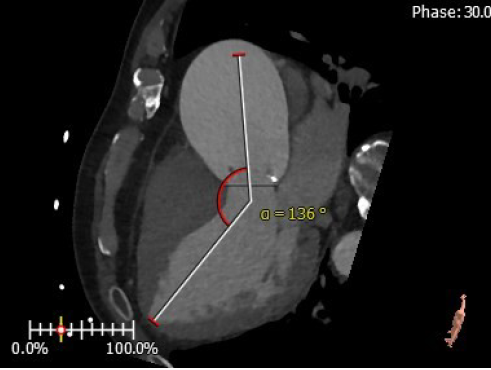

4. 患者术中造影角度LAO:2°,CAU:30°;

主动脉与左心室夹角:136°

术中造影角度:LAO:2°,CAU:30°